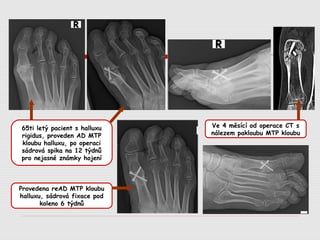

65ti letý pacient s halluxu

rigidus, proveden AD MTP

kloubu halluxu, po operaci

sádrová spika na 12 týdnů

pro nejasné známky hojení

Ve 4 měsící od operace CT s

nálezem pakloubu MTP kloubu

Provedena reAD MTP kloubu

halluxu, sádrová fixace pod

koleno 6 týdnů